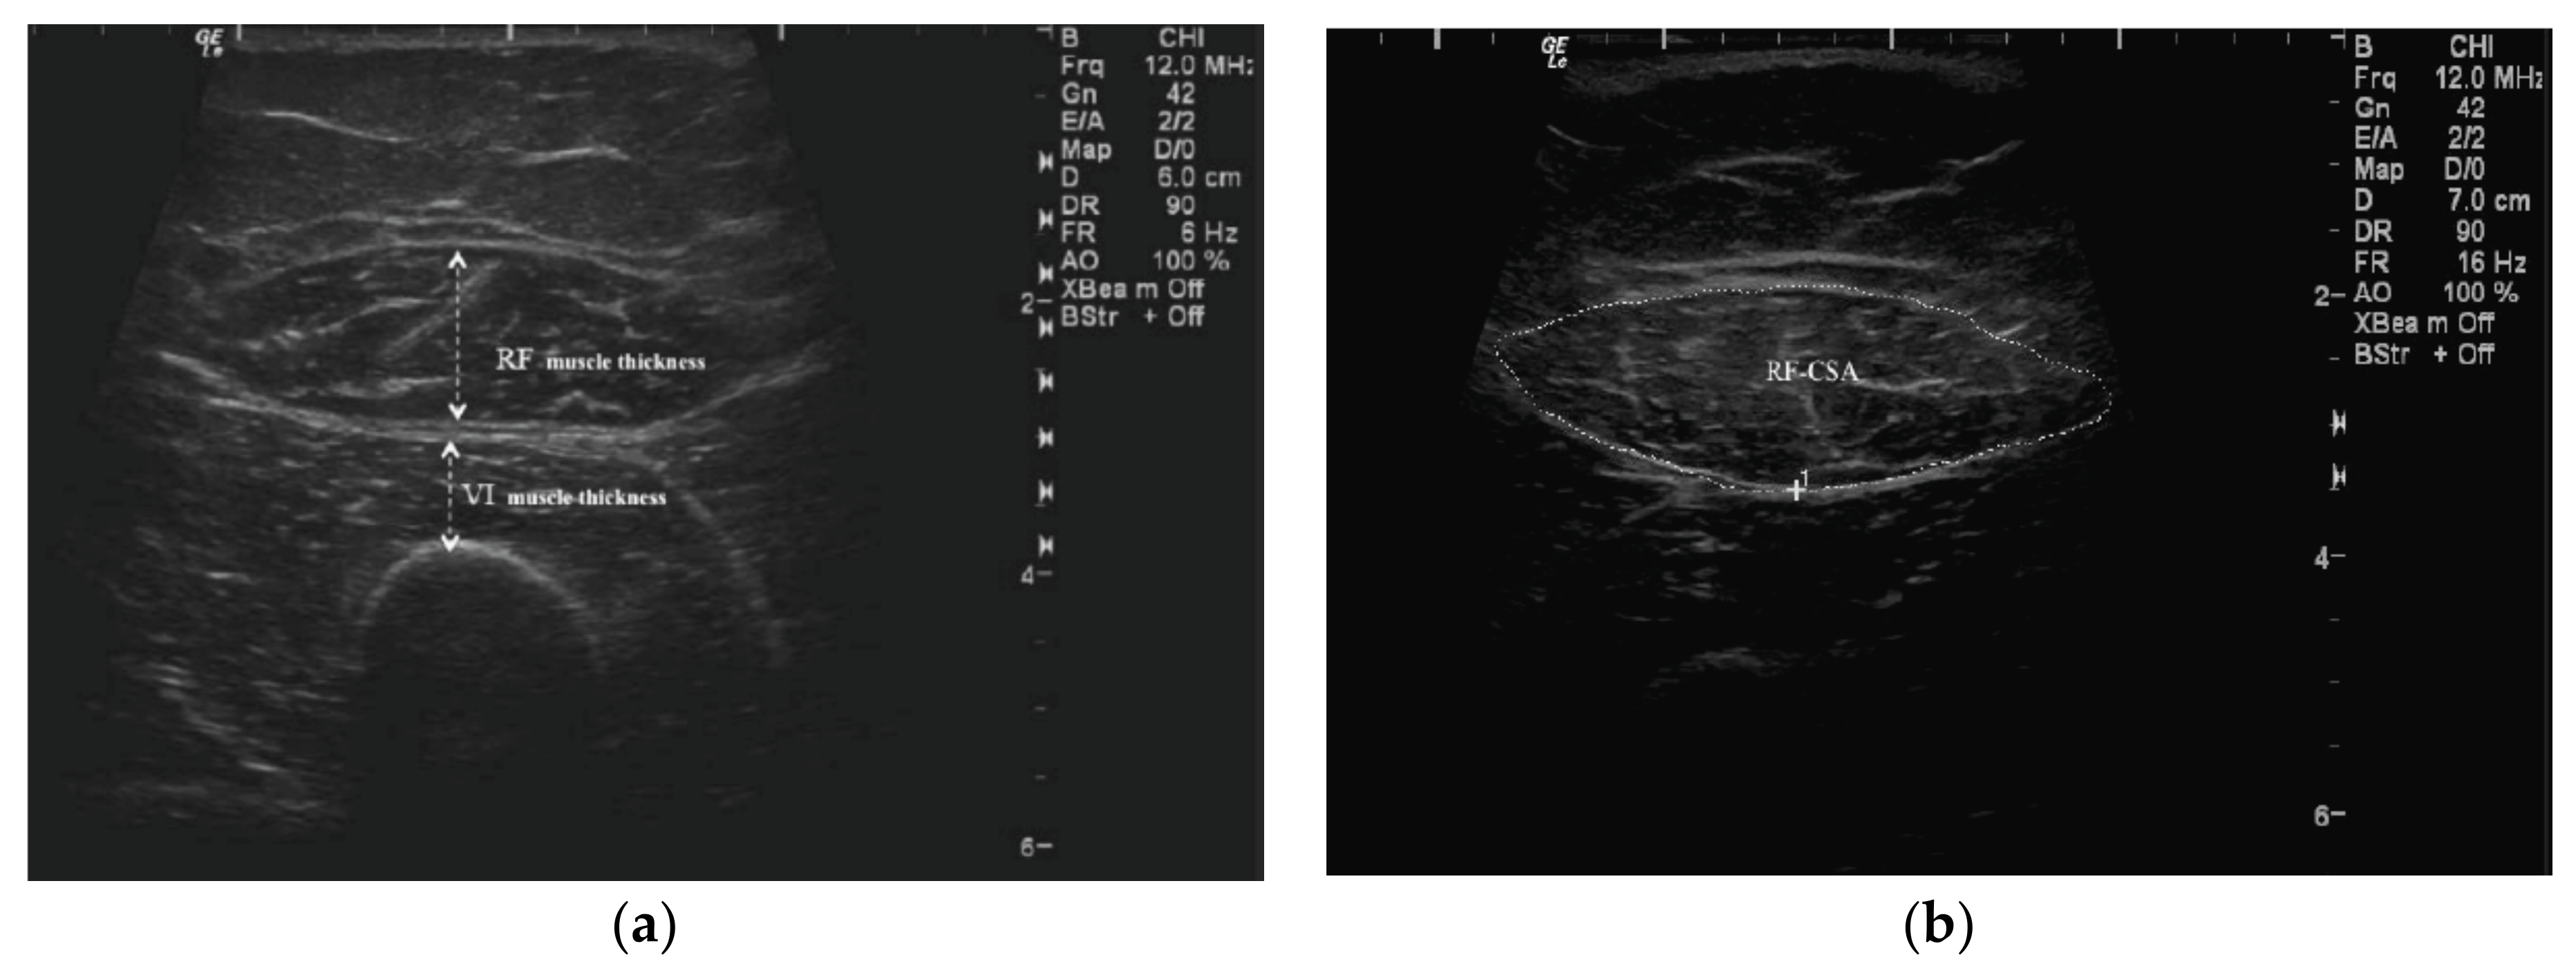

2.2.1. QMT Assessment

2.2.2. RFCSA Measurement